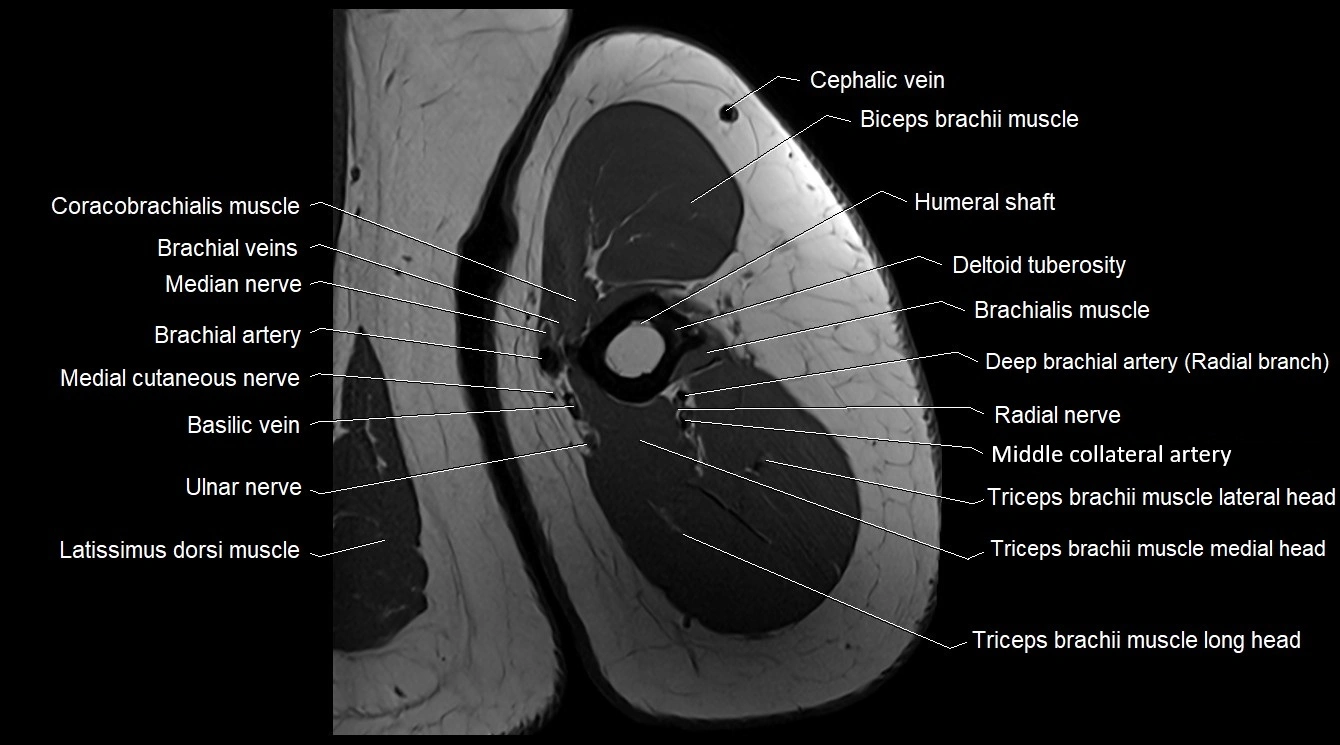

MRI image